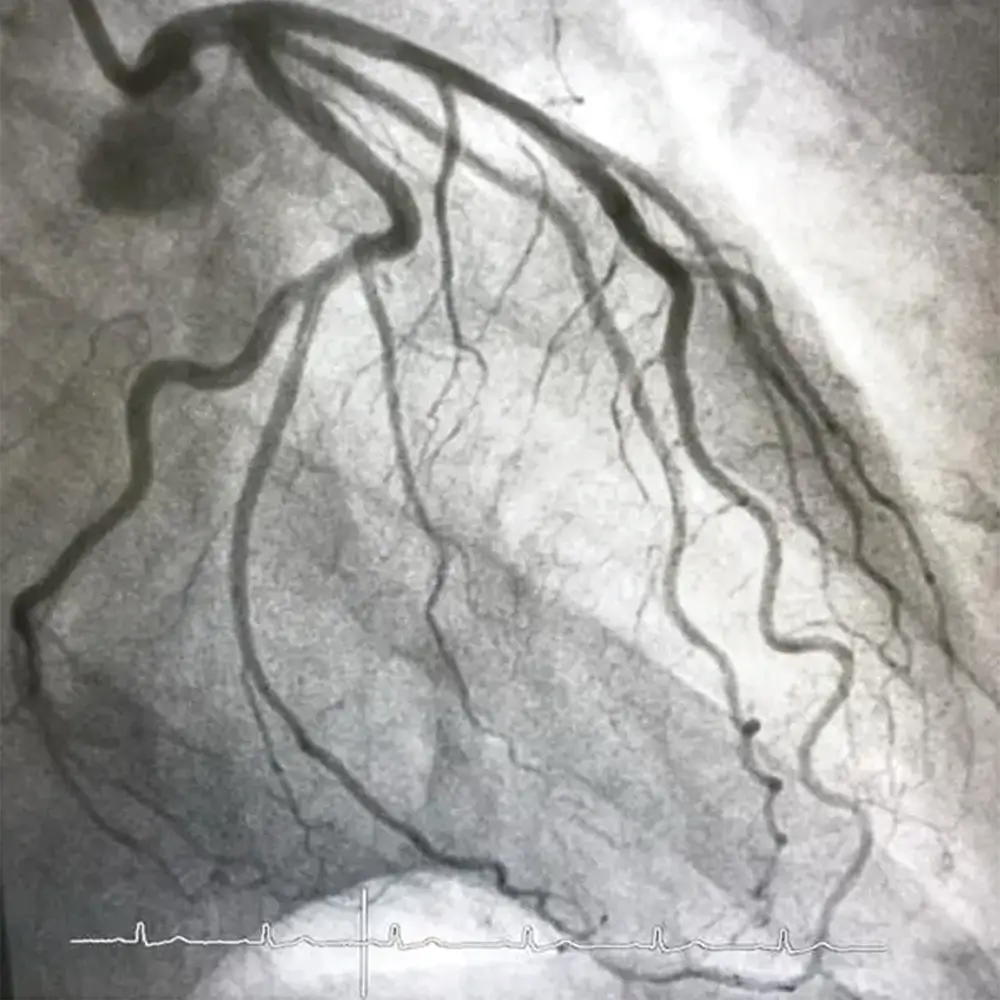

Coronary Angiography

Coronary angiography, also known as cardiac catheterization, is an invasive procedure. A dye is injected into the coronary arteries to visualize blockages or narrowing through X-ray images (angiograms).